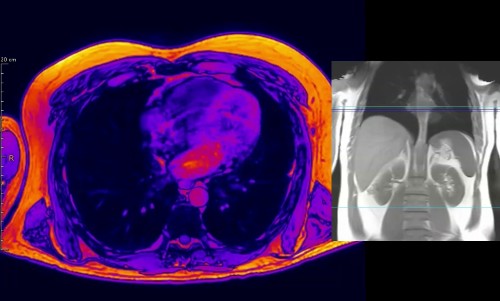

« Éruption stellaire », par Olivier Chancy, Andrew Mitchell, François Bordeleau et Solange Landreville.